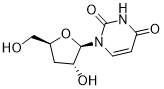

馬鞍山致研生物醫(yī)藥科技有限公司成立于馬鞍山市鄭浦港新區(qū)現(xiàn)代產(chǎn)業(yè)園。公司專(zhuān)注于生物小分子、醫(yī)藥中間體相關(guān)產(chǎn)品的研發(fā)和生產(chǎn),產(chǎn)品主要包括DNA亞磷酰胺單體、RNA亞磷酰胺單體、特殊單體以及按照客戶(hù)要求定制的RNA和DNA,并且公司提供定制合成等方面的研究服...

馬鞍山致研生物醫(yī)藥科技有限公司成立于馬鞍山市鄭浦港新區(qū)現(xiàn)代產(chǎn)業(yè)園。公司專(zhuān)注于生物小分子、醫(yī)藥中間體相關(guān)產(chǎn)品的研發(fā)和生產(chǎn),產(chǎn)品主要包括DNA亞磷酰胺單體、RNA亞磷酰胺單體、特殊單體以及按照客戶(hù)要求定制的RNA和DNA,并且公司提供定制合成等方面的研究服...